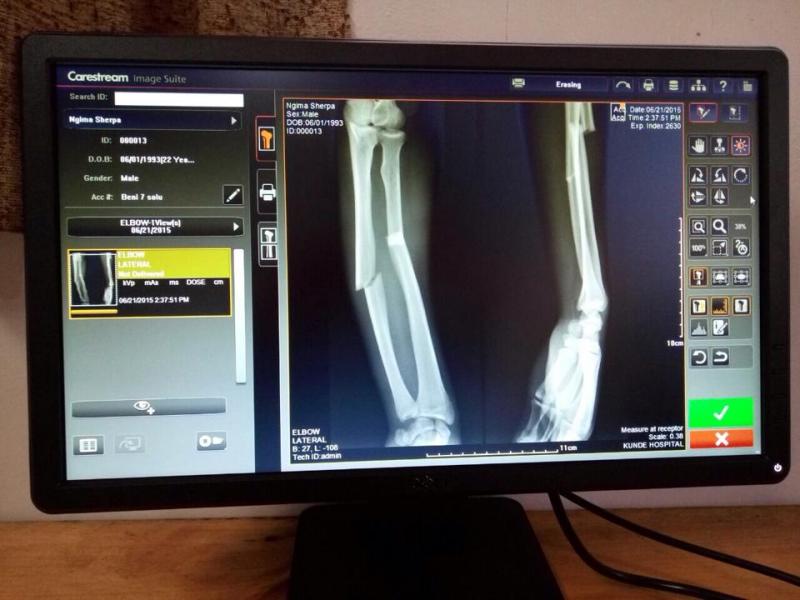

The Carestream Vita Flex CR system is used by medical staff to capture digital X-ray images of shoulders and extremities that have been broken or sprained; the head and neck area to diagnose sprains or concussions; as well as chest exams that may indicate a patient has pneumonia, altitude sickness, or evidence of a heart attack or other serious medical conditions.

“These imaging studies are essential to diagnosing diseases and injuries to climbers, sherpas and other workers at base camp. The images are available in minutes and physicians decide if a patient can be treated at the hospital or must be transported to Kathmandu by helicopter or airplane,” said Charlie Hicks, Carestream’s general manager of global X-ray solutions.